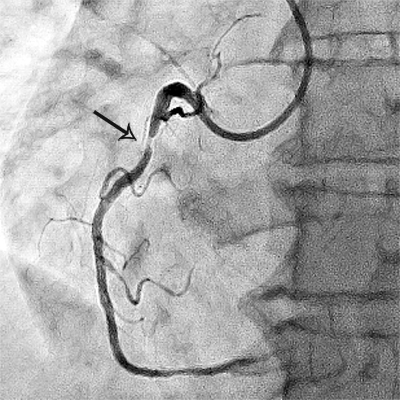

Приклади коронарограм:

стеноз правої коронарної артерії    стеноз лівої коронарної артерії

Звуження (стеноз)

правої коронарної артерії

Звуження (стеноз) гілки

лівої коронарної артерії.